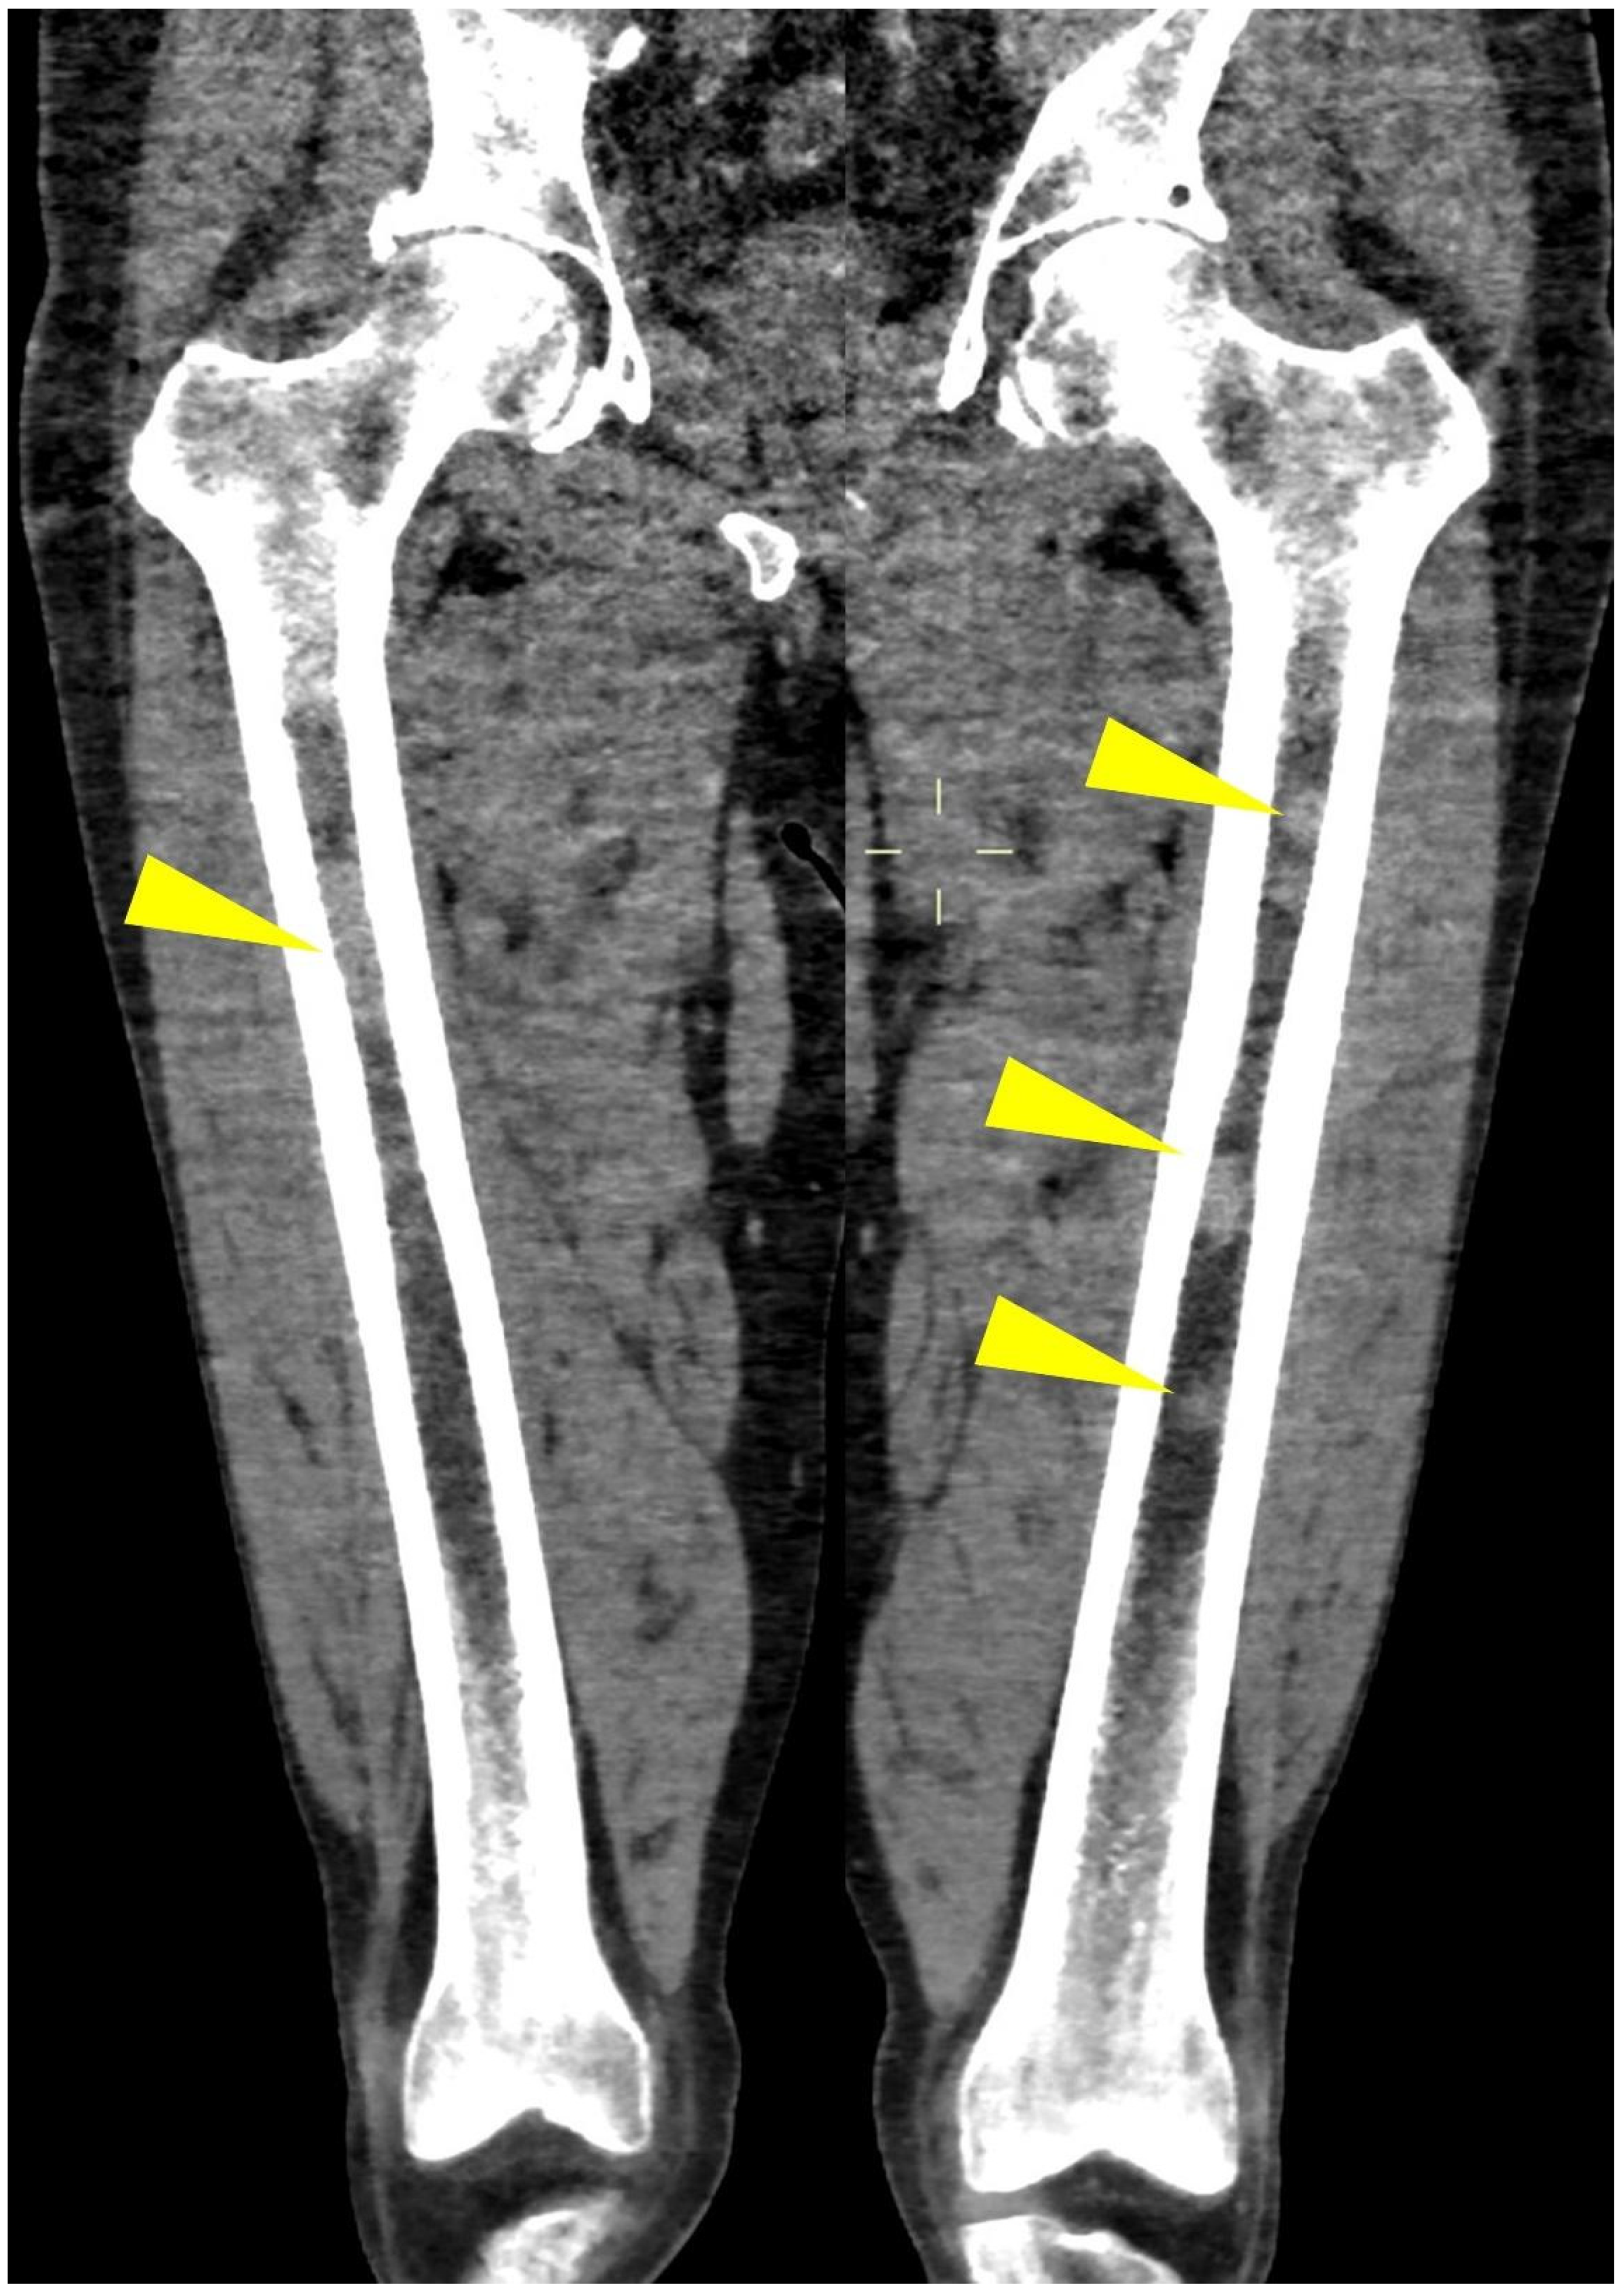

Axial images using a “bone” reconstruction algorithm must be systematically performed, usually in a cranio-caudal fashion, starting from the skull to the cervical, thoracic, and lumbar spine, pelvic bones, and lower limbs, whereas ribs, sternum, scapulae, clavicles, and upper limbs are evaluated afterward (Figure 1B). Once completed, it is advisable to analyze the sagittal multiplanar reconstruction (MPR) images of the spine to identify vertebral fractures and to assess the risk of neural compression (Figure 1C). MPR images are also useful to differentiate benign osteoporotic vertebral fractures from malignant ones (although MRI remains the gold standard for differential diagnosis of vertebral collapse): predictive CT findings of benign vertebral fractures are the presence of fracture lines within vertebral body, retropulsion of a bone fragment from posterior wall into the spine canal, evidence of paraspinal soft tissue widening, and intravertebral “vacuum sign” defined as the presence of an air cleft in the vertebral body. Features associated with malignant vertebral fracture are the presence of extended destruction of the vertebral body (cortex and cancellous bone) and pedicles, as well as a focal soft tissue mass in the paravertebral or epidural space [15]. Focal and/or diffuse intra-medullary infiltration of femur and humerus can be found by analyzing axial and MPR images (Figure 2 and Figure 4) [22].

Figure 4.

Coronal CT image of (yellow arrowheads) bilateral femoral focal intra-medullary high CT density lesions in a patient with MM.

In the long bones of adults, the physiological conversion of hematopoietic bone marrow to fatty bone marrow allows the easy detection of abnormal cell infiltration (diffuse or nodular) with WBLD-CT: most of the intramedullary space of appendicular and axial bones in healthy adults is usually replaced by fatty bone marrow (Figure 9), which in CT imaging evaluation has lower CT attenuation values than the density of water [30,31,32].

When neoplastic cells, as in MM, occupy this space, due to the destruction of mineralized bone, the marrow lesion densities are characterized by solid (myelomatous) tissue that shows positive HU values (Figure 2, Figure 4 and Figure 10) [20].

Infiltration of the humeral and femoral bony canals can be classified as focal or diffuse according to the pattern of the dense area (Figure 2): the diffuse pattern is defined as the homogenous opacity of the bony canal, whereas the focal pattern was defined as the presence of one or more focal high-density areas; evaluating these peripheral medullary deposits on WBLD-CT is critical since they can be linked to high tumor burden, advanced disease stage, and poor prognosis in patients with symptomatic myeloma [18].